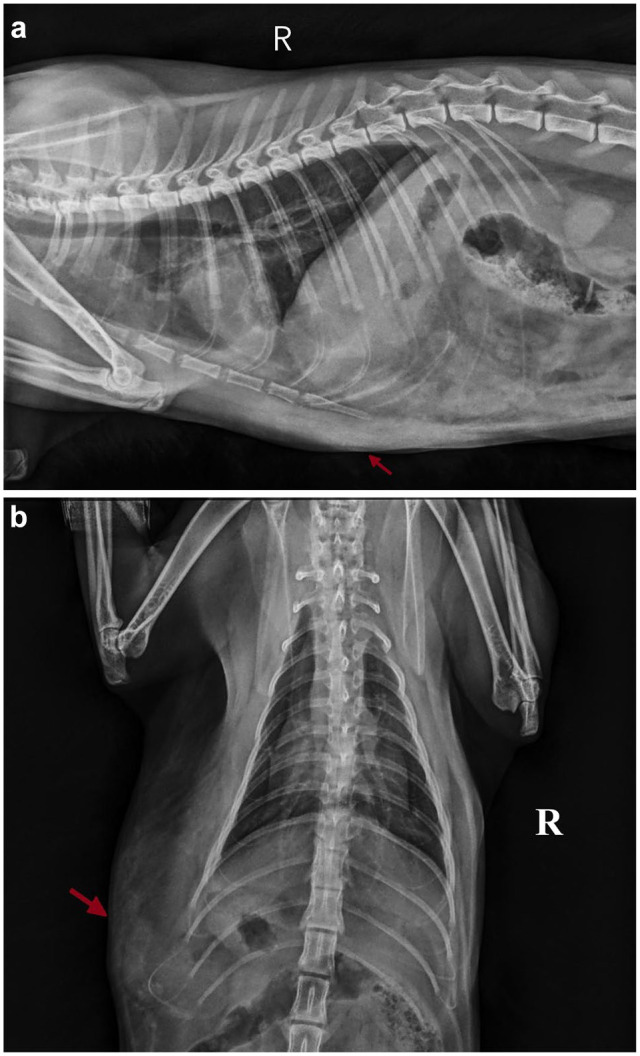

目的本研究的目的是报告与治疗猫肋旁疝相关的结果和并发症,并确定并发膈疝的患病率。方法回顾性分析2019年1月至2024年1月行肋旁疝修补术的猫的医疗记录,进行描述性研究。收集的资料,包括表现、临床体征、手术结果、血液参数、用于诊断的成像技术和术后结果,进行回顾性回顾。进行描述性统计分析。结果共纳入19只猫,中位年龄2岁,年龄范围2个月~ 10岁。入院时的临床症状包括呼吸急促(9/19只猫)、虚弱(7/19只猫)和共济失调或瘫痪(4/19只猫)。x线摄影是主要的诊断工具,89.5%的猫确诊为肋旁疝。并发膈疝出现在63%的病例。9只猫出现术后并发症,其中主要并发症(3/19只猫)导致术后立即死亡。结论和相关性考虑到膈疝的普遍性,本研究强调了在肋旁疝手术中观察膈的重要性。虽然主要并发症导致早期死亡,但大多数患者恢复后没有出现短期并发症。这些发现强调了术后仔细监测的必要性,并强调了猫肋旁疝修复术的良好预后。

ObjectivesThe aim of the present study was to report the outcome and complications associated with the treatment of paracostal hernias in cats and to determine the prevalence of concurrent diaphragmatic hernia.MethodsA retrospective, descriptive study was conducted by reviewing the medical records of cats that underwent paracostal hernia repair between January 2019 and January 2024. The collected data, including presentation, clinical signs, surgical findings, blood parameters, imaging techniques used for diagnosis and postoperative outcomes, were retrospectively reviewed. Descriptive statistical analyses were performed.ResultsA total of 19 cats were included (median age 2 years, range 2 months to 10 years). Clinical signs upon admission included tachypnoea (9/19 cats), weakness (7/19 cats) and ataxia or paralysis (4/19 cats). Radiography was the primary diagnostic tool, identifying 89.5% of the cats with paracostal hernia. Concurrent diaphragmatic hernias were present in 63% of the cases. Postoperative complications occurred in nine cats, including major complications (3/19 cats) leading to immediate postoperative mortality.Conclusions and relevanceConsidering the prevalence of diaphragmatic hernias observed, this study highlights the importance of visualising the diaphragm during paracostal hernia surgery. Although major complications resulted in early death, most patients recovered without short-term complications. These findings emphasise the need for careful postoperative monitoring and highlight the favourable prognosis associated with paracostal hernia repair in cats.